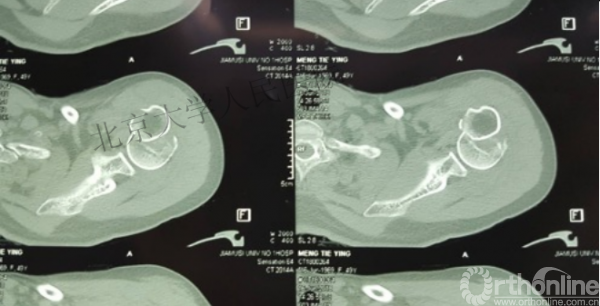

内侧皮质粉碎,低位外科颈骨折,肱骨头-干角维持困难。

术后复位丢失,肱骨头内翻畸形。

能否该偏心固定(钢板)为髓内固定,增加力臂?

另一个留有遗憾的病例,您的选择?PHN?